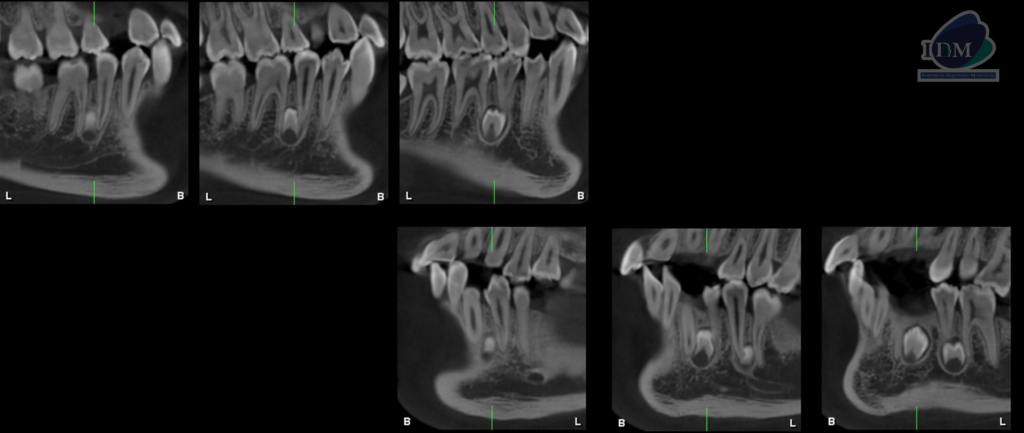

CORTES TANGENCIALES

CORTES TRANSAXIALES

- Supernumerario 1: retenida en posición vertical y en contacto con los segmentos radiculares de las piezas 45 y 46, a nivel apical y orientado hacia lingual.

- Supernumerario 2: retenida en posición vertical y en contacto con los segmentos radiculares de las piezas 33 y 34, a nivel apical y orientado hacia lingual.

- Supernumerario 3: retenida en posición vertical y en contacto con los segmentos radiculares de las piezas 35 y 36, a nivel apical y orientado hacia lingual.